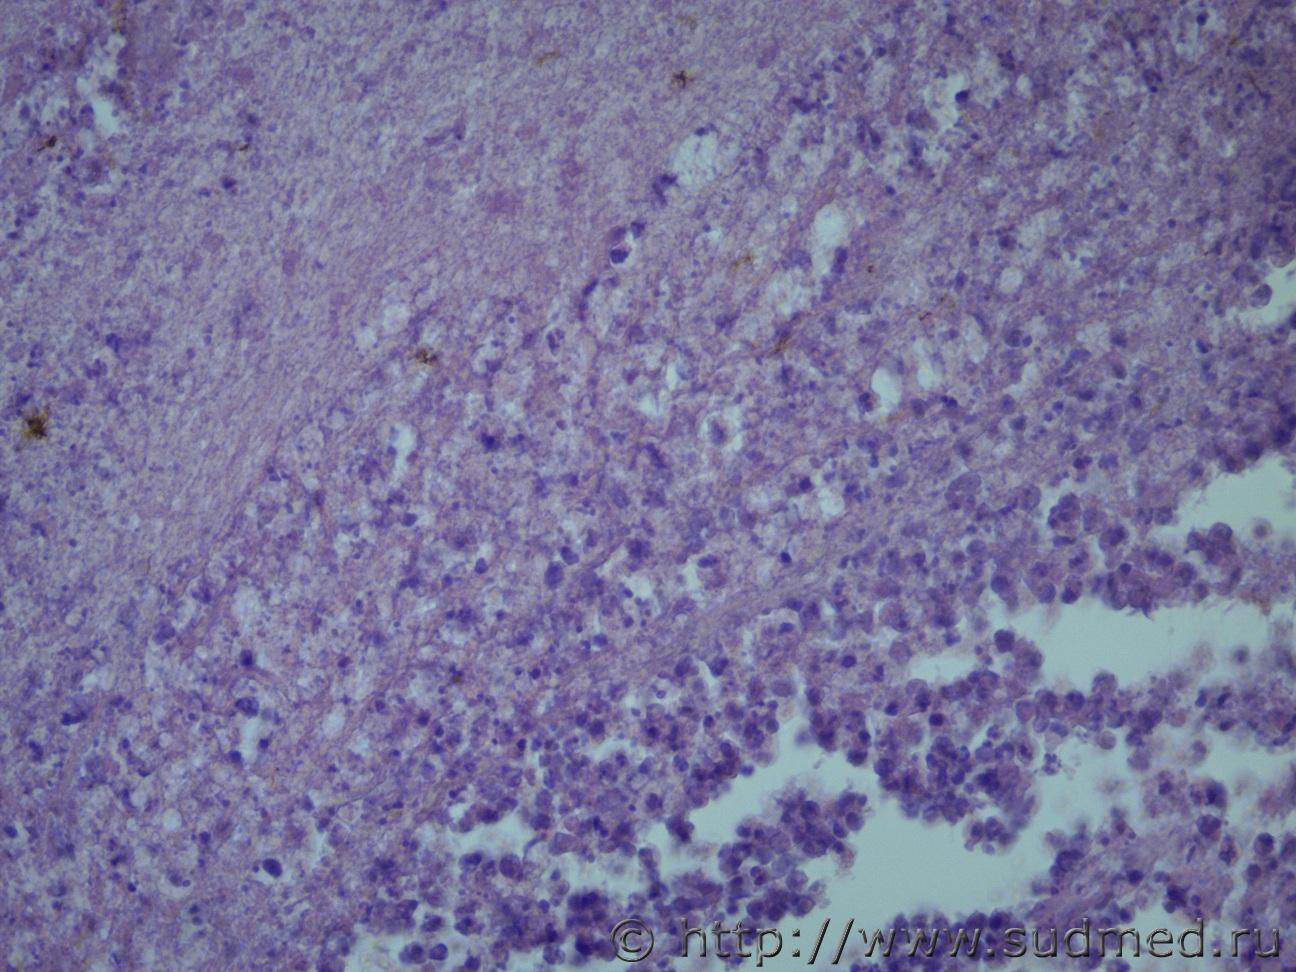

Головной мозг после длительной комы |

IVANNES Головной мозг после длительной комы 23.04.2021 - 12:09

Медик Похожи на криптококки, особенно на 9 фото. 23.04.2021 - 20:39

доктор морфолог Добрый день! Ув. коллеги, нужна ваша помощь. Г... 24.04.2021 - 11:12

Медик Мое мнение за лейкомаляцию

Что это за клетки на фо... 24.04.2021 - 18:58

доктор морфолог Что это за клетки на фото ?

Ув.Медик! Это микр... 25.04.2021 - 20:21